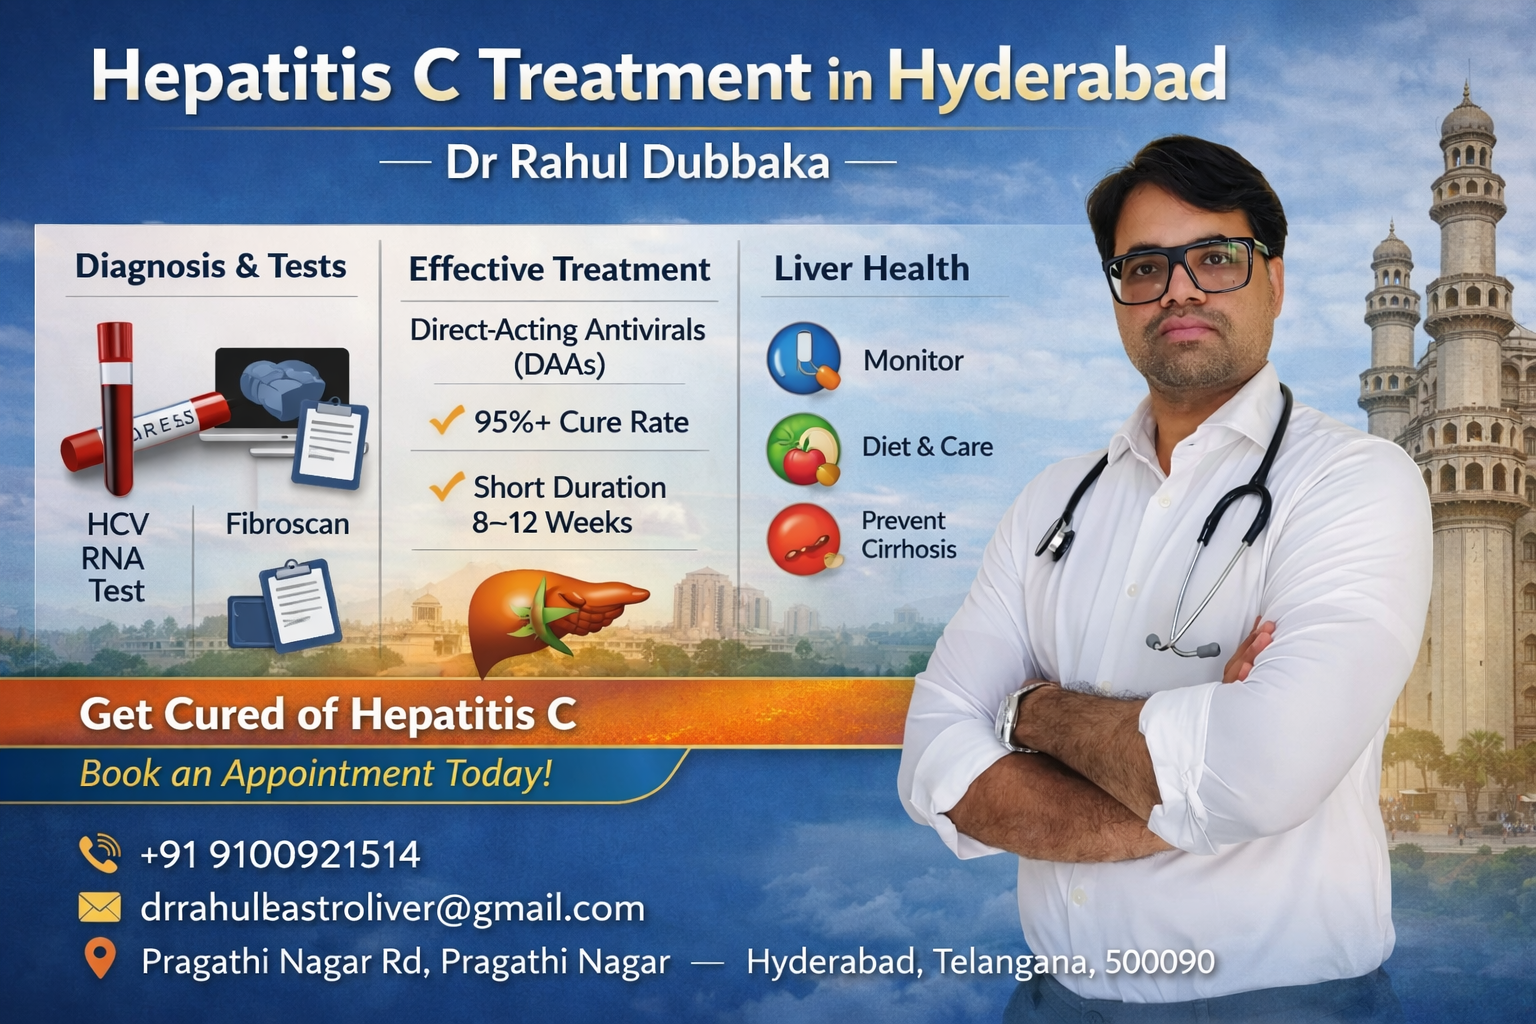

Hepatitis C Treatment in Hyderabad – Expert Care

Looking for Hepatitis C treatment in Hyderabad? Dr Rahul Dubbaka offers advanced antiviral therapy with 95%+ cure rates at People’s Hospital, Pragathi Nagar. Book your consultation today at +91 9100921514. Hepatitis C is a viral infection that primarily affects the liver and can silently damage it over time. If left untreated, it may lead to serious complications such as cirrhosis, liver failure, and even liver cancer. The good news is that with modern medical advancements, Hepatitis C is now highly curable with effective antiviral medications.

If you are searching for Hepatitis C Treatment in Hyderabad, consulting an experienced gastroenterologist and hepatologist like Dr Rahul Dubbaka can ensure accurate diagnosis, personalized treatment, and long-term liver health management.

Dr Rahul Dubbaka practices at People’s Hospital, offering advanced liver care services for patients across Hyderabad.

Why Choose Dr Rahul Dubbaka for Hepatitis C Treatment in Hyderabad?

Dr Rahul Dubbaka is a reputed gastroenterologist and liver specialist with expertise in managing chronic liver diseases.

Key Advantages:

Specialized expertise in liver disorders

Advanced diagnostic facilities

Personalized antiviral treatment plans

Regular monitoring and follow-up

Patient-focused approach

At People’s Hospital, patients receive comprehensive care in a well-equipped medical environment.

Diagnosis of Hepatitis C

Accurate diagnosis is essential before starting treatment.

1. HCV Antibody Test

Detects exposure to the virus.

2. HCV RNA PCR Test

Confirms active infection and measures viral load.

3. Liver Function Tests (LFTs)

Assess liver inflammation and damage.

4. Fibroscan / Ultrasound

Evaluates liver fibrosis or cirrhosis.

5. Genotype Testing

Helps determine the most suitable antiviral regimen.

Modern Treatment Options for Hepatitis C

The introduction of Direct-Acting Antivirals (DAAs) has revolutionized Hepatitis C treatment.

Benefits of DAA Therapy:

8–12 weeks oral medication

Over 95% cure rate

Minimal side effects

No injections required

Safe for most patients

Book Your Hepatitis C Consultation Today

If you or a loved one has been diagnosed with Hepatitis C, consult Dr Rahul Dubbaka at People’s Hospital for expert evaluation and advanced treatment.

📍 People’s Hospital

Plot No. 755A, 1st Floor, Pragathi Nagar Rd,

Near Three Monkeys Statue, Pragathi Nagar,

Hyderabad, Telangana 500090

📞 +91 9100921514

📧 drrahulgastroliver@gmail.com